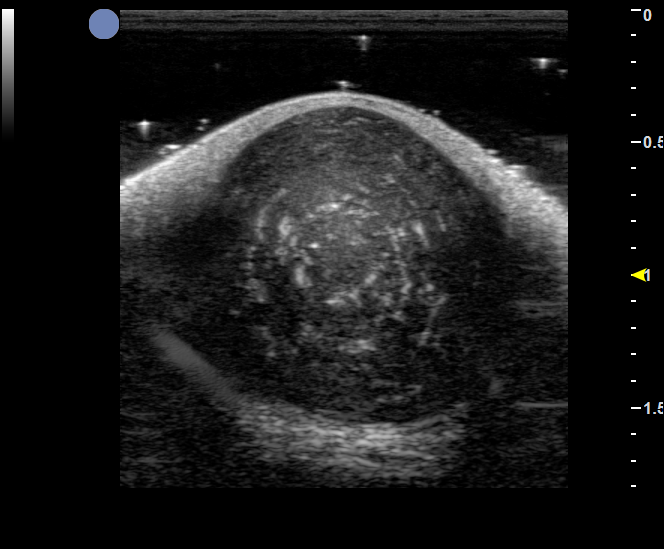

增殖期血管瘤